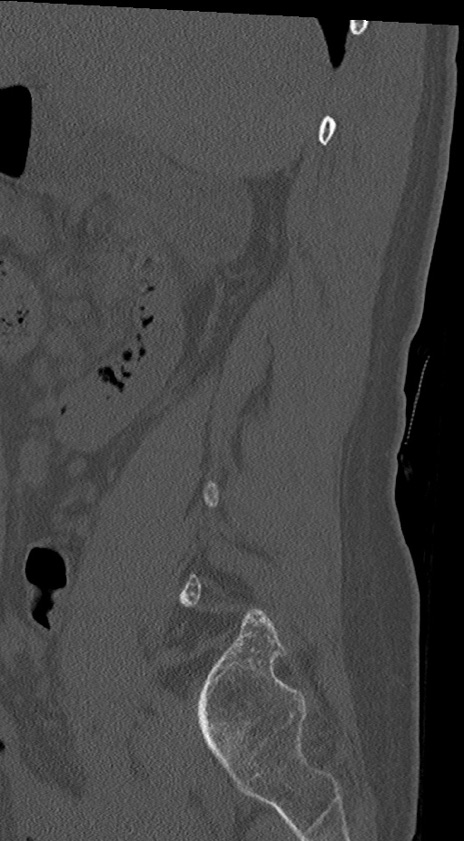

【整形】TIPS症例4 腰椎CT(矢状断像)

腰椎CT

冠状断像